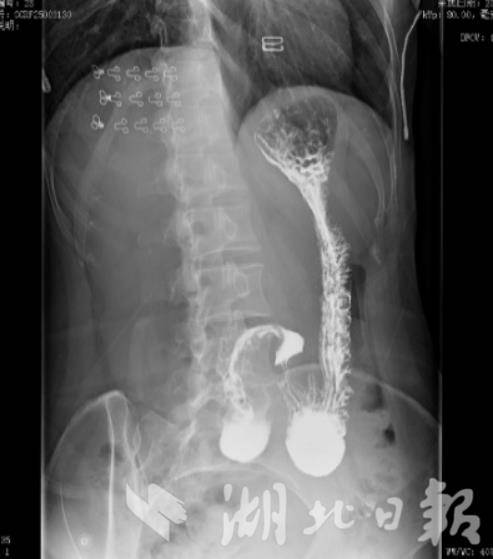

术后上消化道造影

经术前评估,团队为黄女士实施微创腹腔镜下改良胃固定术。手术仅在腹部打4个0.5-1厘米小孔,医生借助腹腔镜镜头,用补片替代肝胃韧带并精细缝合固定,既预防胃体再次下垂,又不影响胃蠕动。整台手术耗时1小时,出血量微乎其微,大幅降低了创伤与术后并发症的风险。

术后,团队为黄女士定制了中西医结合康复方案。营养师规划循序渐进的膳食方案,从流质饮食起步改善营养不良;同时开具由党参、黄芪等组成的健脾和胃方剂,调理气血、升阳举陷;搭配西医药物提升消化功能、降低内脏敏感性。术后一周,黄女士已能正常吃一碗稀米粥,腹胀感逐渐减轻;术后一个月复查,体重回升3斤,也能正常平躺睡觉。